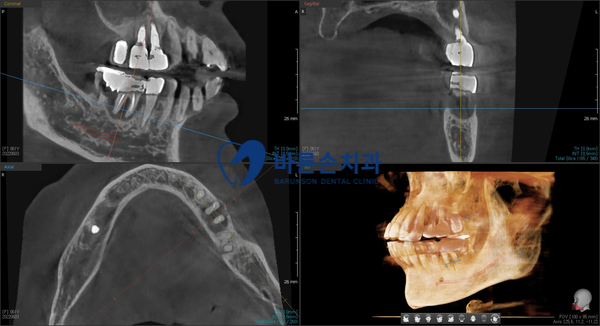

임플란트 수술 전 3D-CT 촬영을 통해

환자분의 치조골(뼈) 상태 정확하게 확인 후

그에 맞는 뼈이식과 임플란트의 식립 위치와 방향을

미리 계획하고 수술을 진행하게 됩니다

환자분의 경우 CT 촬영을 통해 알 수 있다시피

오래된 염증으로 인한 치조골의 손상이 심하셔서

많은 양의 뼈이식이 필요해 보이네요